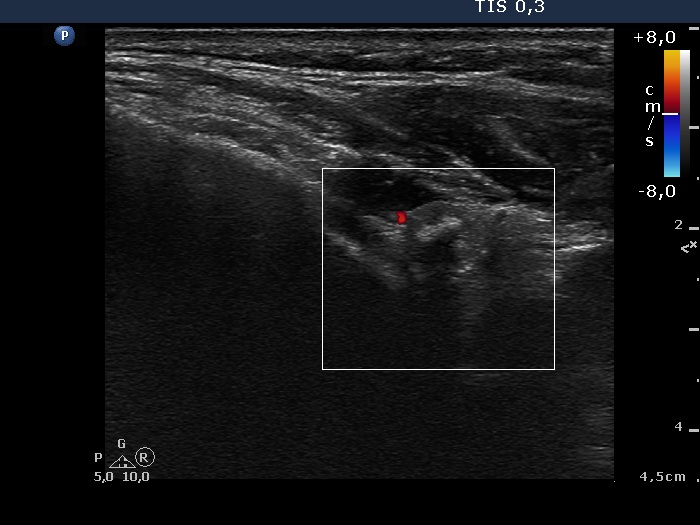

Ultrasonography: A large lesion composed of multiple moderately hypoechogenic and hyperechogenic nodules occupied almost the entire right lobe. There was a small hypoechogenic nodule in the upper pole while a cystic nodule in the central part of the left lobe. The former presented coarse and microcalcifications, too. The vascularization was not specific.